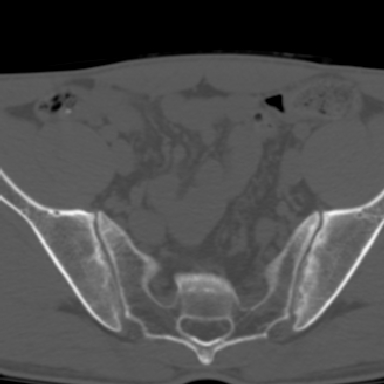

m 30 腰背部不适半年; 清晨时僵硬; 活动症状有所改善

双侧骶髂关节下2/3关节面模糊,毛糙,可见小囊状骨质破坏区.支持强直性脊柱炎.

强直性脊柱炎的早期改变!不仅表现为双侧骶髂关节,第5腰椎与骶椎间的关节突关节也有类似改变。

双侧骶髂关节下2/3关节面模糊,毛糙,髂骨侧可见小囊状骨质破坏区,骶髂关节间隙增宽(软骨破坏期)。支持早期强直性脊柱炎。

双侧骶髂关节下2/3关节面模糊、毛糙,可见小囊状骨质破坏区,呈虫咬状改变,周围可见增生硬化.支持强直性脊柱炎早期表现.

双侧骶髂关节髂骨面硬化,毛糙,小囊变,属于早期强直性脊柱炎